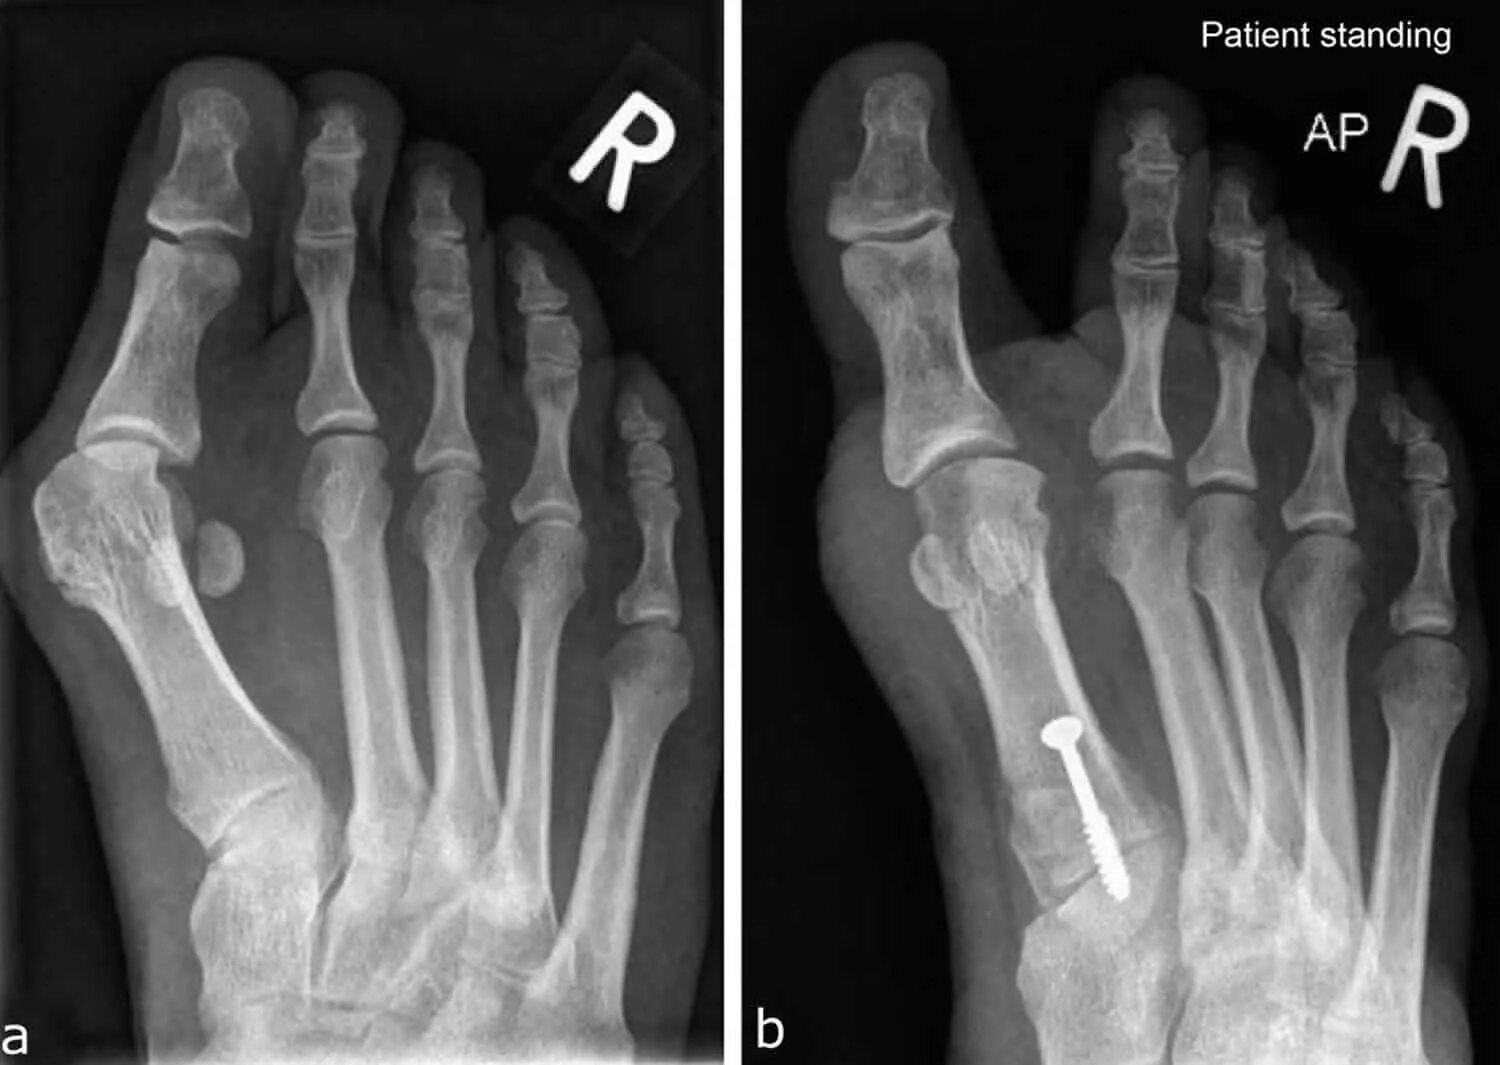

Степени вальгусной деформации